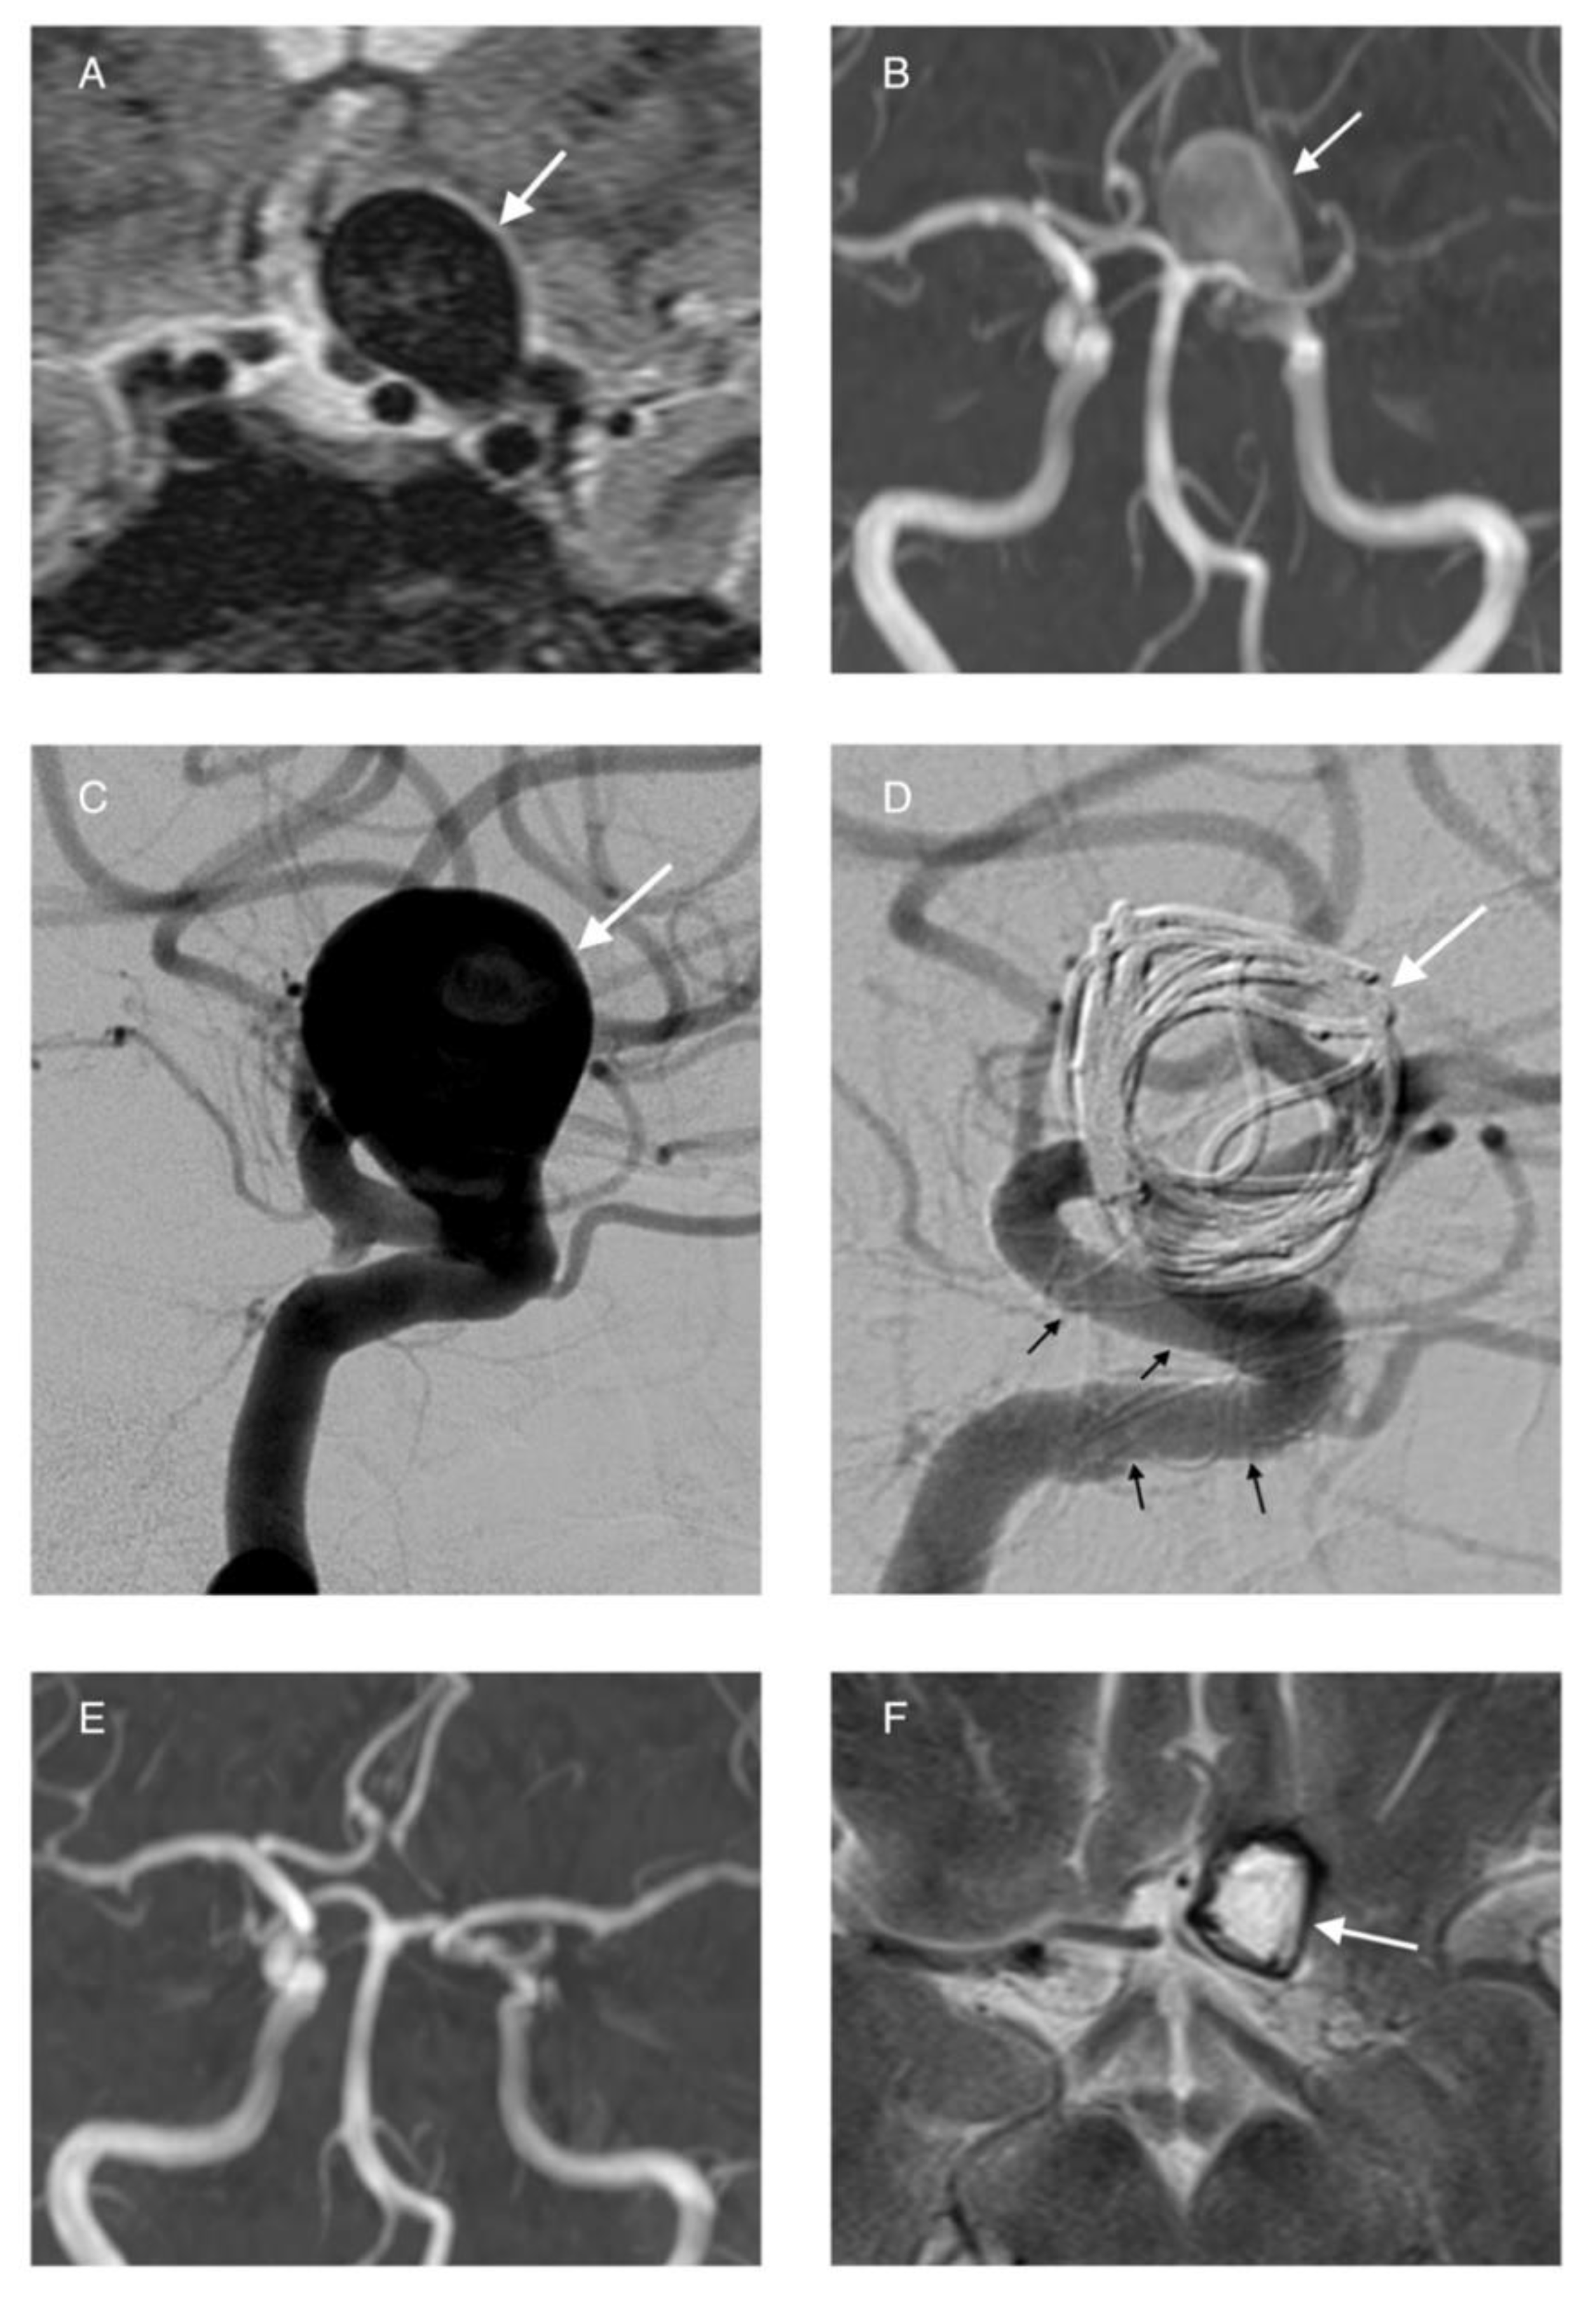

3.5. Flow Diversion